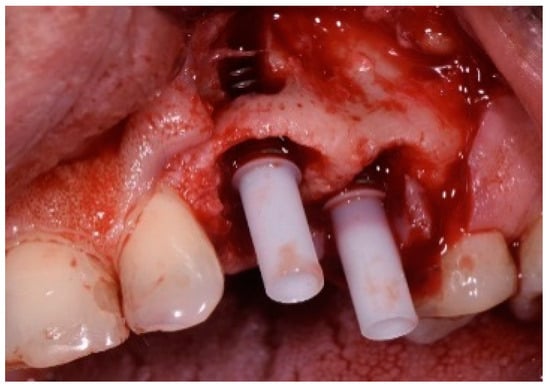

A 51-year-old male patient in good health and a non-smoker presented with a fractured maxillary canine with recurrent subgingival caries, and a failing root canal on the maxillary first premolar (Figure 18). The treatment plan consisted of the extraction of both teeth #11 and #12 roots, followed by the placement of implants. The preoperative surgical protocol described in patient 1 was followed. Figure 19 represents the residual boney defect associated with this area after implant placement. Similar to the previous cases, graft material was placed, and the area was closed for healing. Chairside temporary crowns were fabricated, followed by the placement of zirconia crowns in six months. Figure 20 represents the area three years after treatment.

Figure 18.

Clinical view of fractured tooth #11 and existing crown on tooth #12.

Figure 19.

Clinical view of implants and boney defects.